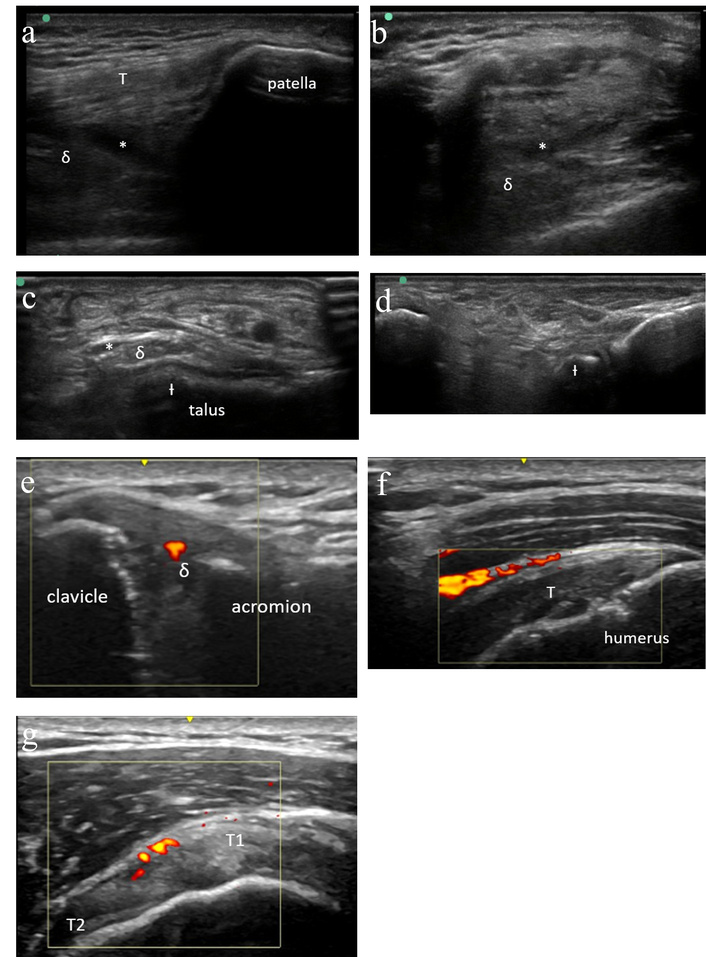

Patient 2 is a 53-year-old male who first presented with new joint pain beginning about two weeks after his ninth cycle of pembrolizumab for metastatic melanoma. He reported first developing pain in both knees followed by the onset of pain in his ankles followed by his shoulders, elbows, and hips. He was advised by his oncologist to begin taking ibuprofen, which provided only partial relief. He was referred to rheumatology for further evaluation. At his initial consultation, he described inflammatory symptoms with significant stiffness with inactivity and improvement in pain and stiffness with activity. On exam, he was noted to have tibiotalar fullness without associated tenderness, and no other joints were suspicious for synovitis. Diagnostic ultrasound was performed of the knees and ankles with findings of small knee effusions without synovial hypertrophy, and synovial hypertrophy of both ankles without associated hyperemia (Figure 2a–d). Synovial fluid had 26 white blood cells/μL.

Case 2 ultrasound images. (a) Left knee ultrasound (suprapatellar longitudinal) demonstrating small effusion (*) with minimal synovial hypertrophy (δ) and normal quadriceps tendon (T). (b) Left knee ultrasound (suprapatellar transverse) demonstrating small effusion (*) with minimal synovial hypertrophy (δ). (c) Right ankle (anterior transverse) ultrasound demonstrating grade 2 synovial thickening (δ) and trace effusion (*) as well as moderate cortical irregularity (Ɨ) and scattered calcifications. No tenosynovitis. (d) Right subtalar ultrasound without synovitis. Moderate cortical irregularity (Ɨ) and scattered calcifications noted. (e) Right acromioclavicular joint ultrasound demonstrating grade 2 synovial thickening (δ) of the acromioclavicular joint with positive power Doppler signal. (f) Right shoulder ultrasound demonstrating increased hyperemia at the subdeltoid bursa overlying the supraspinatus tendon (T). (g) Right shoulder ultrasound demonstrating increased hyperemia in the rotator cuff interval between the anterior supraspinatus (T1) and the long head of the biceps tendon (T2).

Given his mixed clinical picture, he was advised to begin a prednisone taper starting at 20 mg daily. Within 24 hours, he noted near-resolution of joint pain, worsening as he tapered. Repeat ultrasound was performed with resolution of previously noted synovial hypertrophy and effusions. He was transitioned to scheduled ibuprofen with ongoing symptom control. A repeat ultrasound then demonstrated only mild re-accumulation of right ankle effusion and synovial fullness but no active synovitis and no recurrent effusions in the knees. He was then advised to begin as-needed ibuprofen, and he resumed pembrolizumab. Unfortunately, his pembrolizumab infusion was followed by worsening pain in his hands, elbows, and shoulders, again improving with reintroduction of prednisone and ibuprofen. Ultrasound was again performed, now demonstrating obvious synovitis involving the right acromioclavicular joint as well as abnormal hyperemia in the rotator cuff interval consistent with tendonitis (Figure 2e–g).

Based on these findings that were consistent with ICI-inflammatory arthritis, he was then started on sulfasalazine as well as increased prednisone dosing. Subsequently, he was able to complete his planned ICI course while slowly tapering off of prednisone. He ultimately tapered off of sulfasalazine the following year without recurrent joint symptoms.

This case illustrates several important concepts in the management of ICI arthritis. First, it demonstrates the utility of MSKUS in distinguishing between activated osteoarthritis and ICI-inflammatory arthritis. This distinction is important as these conditions are treated differently. Additionally, this case demonstrates that patients with ICI-inflammatory arthritis may not initially present with findings such as synovial hyperemia or elevated synovial fluid nucleated cell counts. Finally, this demonstrates the use of MSKUS in evaluating treatment response and its utility in guiding treatment decisions, such as whether to maintain steroid therapy or introduce a disease-modifying antirheumatic drug. While this patient was treated with sulfasalazine with benefit, it is now known that there is a high rate of sulfasalazine intolerance (including hypersensitivity reactions) in ICI patients, and so we avoid this agent when possible [10, 11].